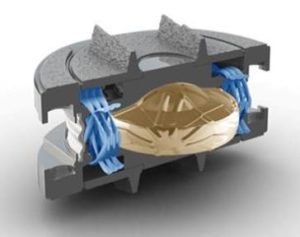

Unlike early Disc Replacement designs, the Spinal Kinetics M6 artificial disc is designed to replicate the structure and performance of a natural disc. Its innovative design incorporates an artificial nucleus to allow shock absorption and a woven fiber annulus for graded variable motion resistance in all directions.

These characteristics accurately replicate the natural disc, allowing the implant to work in concert with the remaining human discs. Unlike earlier “ball-in-socket” implants, with the M6 disc replacement the resulting natural functionality of the entire spinal curve will provide the best chance for a full recovery. In addition, future complications will be eliminated by reducing adjacent level degeneration and strain on the muscles and ligaments.

Engineered to replicate your own disc, the M6 disc replacement is the only artificial disc that incorporates an artificial nucleus (made from polycarbonate urethane) and a woven fiber annulus (made from polyethylene). The M6 artificial disc nucleus and annulus are designed to provide the same motion characteristics of a natural disc.

Together, the M6’s artificial disc nucleus and annulus provide compressive capabilities along with a controlled range of natural motion in all 6 degrees of freedom along each vertebra.

The M6 disc replacement has two titanium outer plates with keels for anchoring the disc into the bone of the vertebral body. These outer plates are coated with a titanium plasma spray that promotes bone growth into the metal plates, providing long term fixation and stability of the disc in the bone.